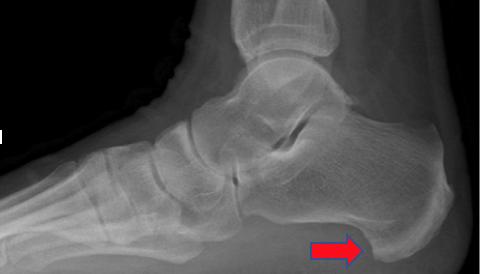

跟骨骨刺关节镜下切除术后